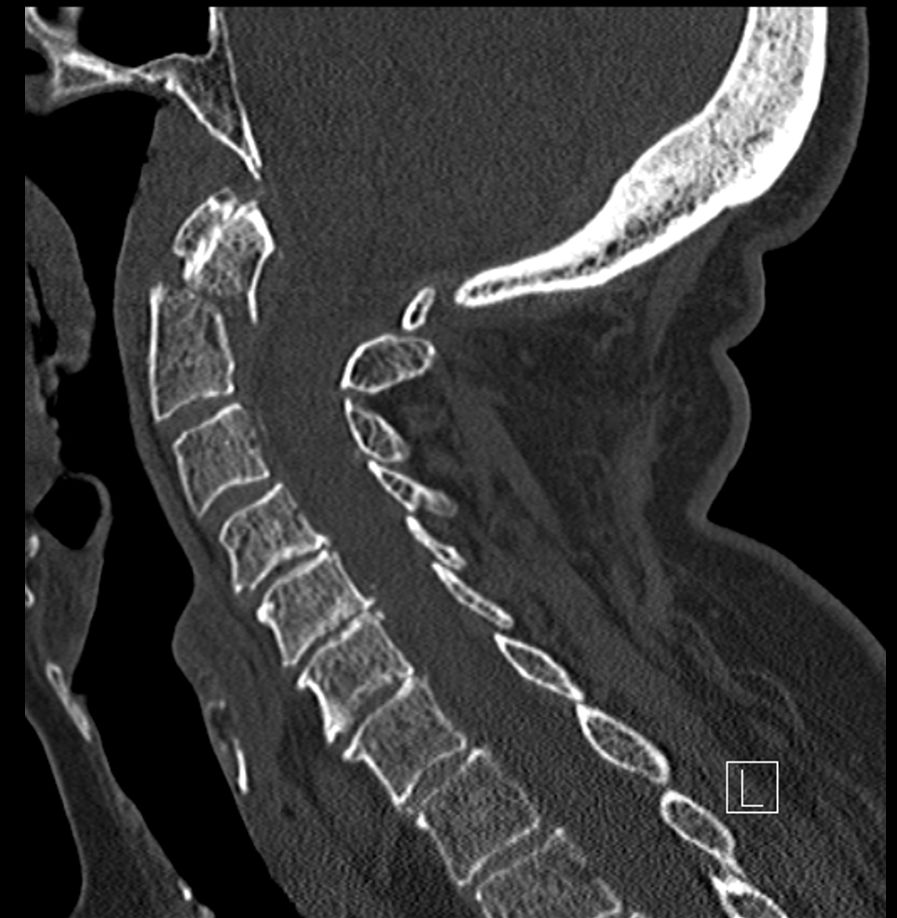

CT

CT (počítačová tomografie) je skvělé na zobrazení kostí a přesné určení, kde je zlomenina a o jaký typ se jedná.

U pacientů s více zraněními (polytrauma) se RTG často přeskakuje a rovnou se dělá CT (celé páteře, protože je to rychlejší a detailnější. Pokud je poranění méně závažné, CT se zaměřuje jen na postiženou oblast, přičemž se prohlédne alespoň tři obratle nad a pod místem zranění.

Jestliže po úrazu se manifestují neurologické potíže, jako je brnění, slabost nebo ztráta citlivosti, doplňuje se magnetická rezonance (MR), která detailně zobrazí měkké tkáně a zmapuje vnitřek páteřního kanálu. U dětí se MR dělá hned jako druhé vyšetření a CT až dle toho, co MR odhalí, aby se minimalizovala radiační zátěž.